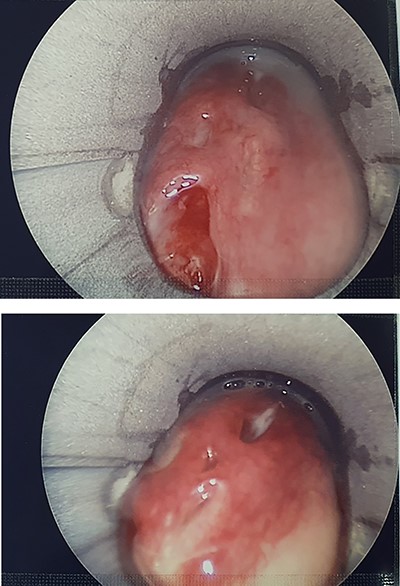

Subsequent pan-endoscopy and neck exploration confirmed multiple slit-like four or five mucosal perforations in left posterior pharyngeal wall and left piriform fossa with muco-purulent discharge (Fig. 4). Two corrugated drains, one directed inferiorly towards pharynx and one superiorly, were secured. Histology of tissue biopsy confirmed acute and chronic inflammation with granulation, which was negative for dysplasia, malignancy and cytomegalovirus, fungal, acid-fast bacilli infections. No microbial growth was obtained from culture.

Pharyngoscopy showing slit-like mucosal perforations in left posterior pharyngeal wall and left piriform fossa with muco-purulent discharge.

He was managed conservatively. Two days post-operatively, surgical emphysema had resolved and there was minimal drain output. Contrast swallow 6 days post-operatively showed aspiration and repeat pharyngoscopy, 10 days post-operatively, showed healing perforations (Fig. 5).